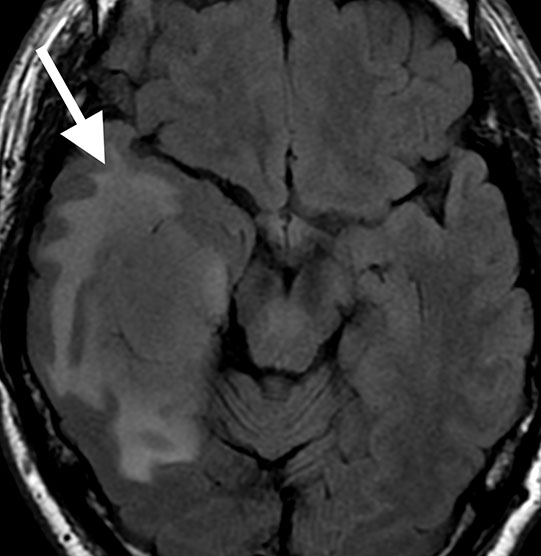

【症例報告】60代前半の男性。約1ヶ月前から右前頭部の重い感じの痛みがあり受診。頭痛は朝起きた時に強く感じる傾向がありました。

MRI検査では、

頭痛が1週間以上続く原因

右側頭葉に直径約6cmの脳腫瘍を認めました。

精密検査が必要であり、大学病院へ紹介。腫瘍の種類は悪性リンパ腫と診断され、化学療法を行いました。